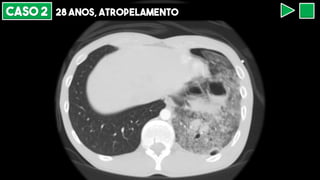

CASO 2 28 ANOS, ATROPELAMENTO

LACERAÇÃO PULMONAR